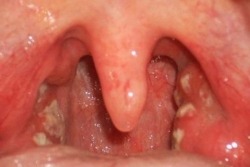

5 biện pháp cần thực hiện để phòng bệnh bạch hầu

Cục Y tế dự phòng Bộ Y tế cho biết,đến nay, tại huyện Krông Nô đã qua 16 ngày không ghi nhận trường hợp mắc mới và tại huyện Đắk Glong đã qua 4 ngày ...